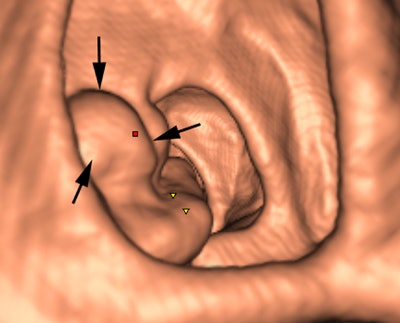

CAD for colonography has shown particular promise, and most radiologists will come across it in their workflow and will need to understand sensitivity and specificity issues, as well as when CAD should be deployed in this area. The technique's major diagnostic benefits are in small 6- to 9-mm polyps, which often are difficult for the radiologist to spot.

"CAD acts like a spell-check for small polyps," said Dr. Stuart Taylor, professor of medical imaging and consultant gastrointestinal radiologist at University College London, in an interview ahead of the congress. "There are also instances when tumors and large polyps are missed by the radiologist before CAD draws attention to them."

False negatives can present a challenge too. Typically the computer program looks for the rounded bowler-hat contours of a polyp that stand proud of the bowel wall. It may miss the flatter polyps and even large mass-like lesions that don't have typical rounded contours.

Most manufacturers are further developing CAD using validated CT colonography cases containing examples of unusually shaped flat lesions and also cancers, writing these characteristics into their software and training their programs to recognize them. The diagnostic capacity of CAD is, therefore, continually improving.